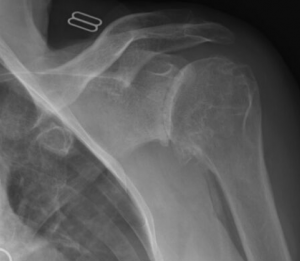

Een goed klinisch onderzoek door de arts is essentieel om de diagnose te vermoeden en op te sporen of er sprake kan zijn van begeleidende zenuw letsels. Een klassieke radiografie toont de ontwrichting en ook eventuele bijkomende letsels bv. breuken. In tweede fase en zeker bij recidiverende ontwrichtingen zal bijkomend een CT scan of MRI scan met contrast gepland worden om de schade aan het kapsel, de ligamenten en het labrum in beeld te brengen.

- Een klassieke radiografie toont de ontwrichting en ook eventuele bijkomende letsels bv. breuken